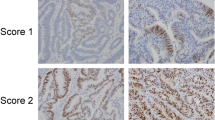

β-Catenin staining was evaluated as previously described [15]. The results were calculated as IHC scores, where IHC score = percentage of nuclear positive cells × staining intensity. Nuclear staining was classified into five grades from 0 to 4. We defined staining intensity as follows: 0, negative; 1, weak; 2, moderate; 3, strong; and 4, very strong. The nuclear β-catenin IHC score ranged from 0 to 400. The number of CD8+ TILs was calculated in the three most infiltrated fields for each case using an intermediate-power field.

Correlation between LGR5 expression and β-catenin expression

Previous studies on CRC showed that β-catenin is related to LGR5, a cancer stem cell marker [17], and that β-catenin induces expression of LGR5 [18]. We thus analyzed the correlation between LGR5 H-score and expression of nuclear-translocated β-catenin. Mean nuclear β-catenin IHC scores in MMR-P cases and MMR-D cases were 104.5 (81.3–285.8) and 23.9 (9.9–77.1), respectively. Nuclear β-catenin IHC scores in MMR-D cases were significantly lower than those in MMR-P cases (P = 0.002). In all cases, there was a positive correlation between LGR5 H-score and nuclear β-catenin IHC score (r = 0.728, P < 0.001) (Fig. 4). Even in MMR-D and MMR-P cases, there was a positive correlation between LGR5 H-score and nuclear β-catenin IHC score (r = 0.692, P = 0.013 and r = 0.679, P = 0.003, respectively) (Fig. 4).